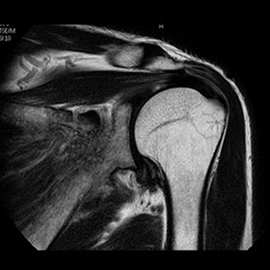

MRIの検査画像例

MRI

PHILIPS社製Ingenia 1.5TMRIを使用しています。開口径が従来の装置より広いワイドボアタイプとなり、より圧迫感の少ない、患者さんに優しい検査環境を実現できます。また、世界初のデジタルコイルを採用しており、ノイズが少なく診断能の高い画像が得られるようになりました。

新しい技術として、体動補正技術(MultiVane)や金属アーチファクト抑制技術(MARS)が使えるようになり、画質が格段に改善しております。

また、これまでの呼吸同期に加え、横隔膜の動きをリアルタイムに観察できるNavigator echo法が使えるようになり、肝臓領域やMRCP検査においてより高精細な同期撮影が可能となりました。

また、全脊椎検査やDWIBSなど以前の装置では多くの時間を費やしていた広範囲の検査に対して特にスループットが向上し、以前よりも短時間での検査が可能となりました。